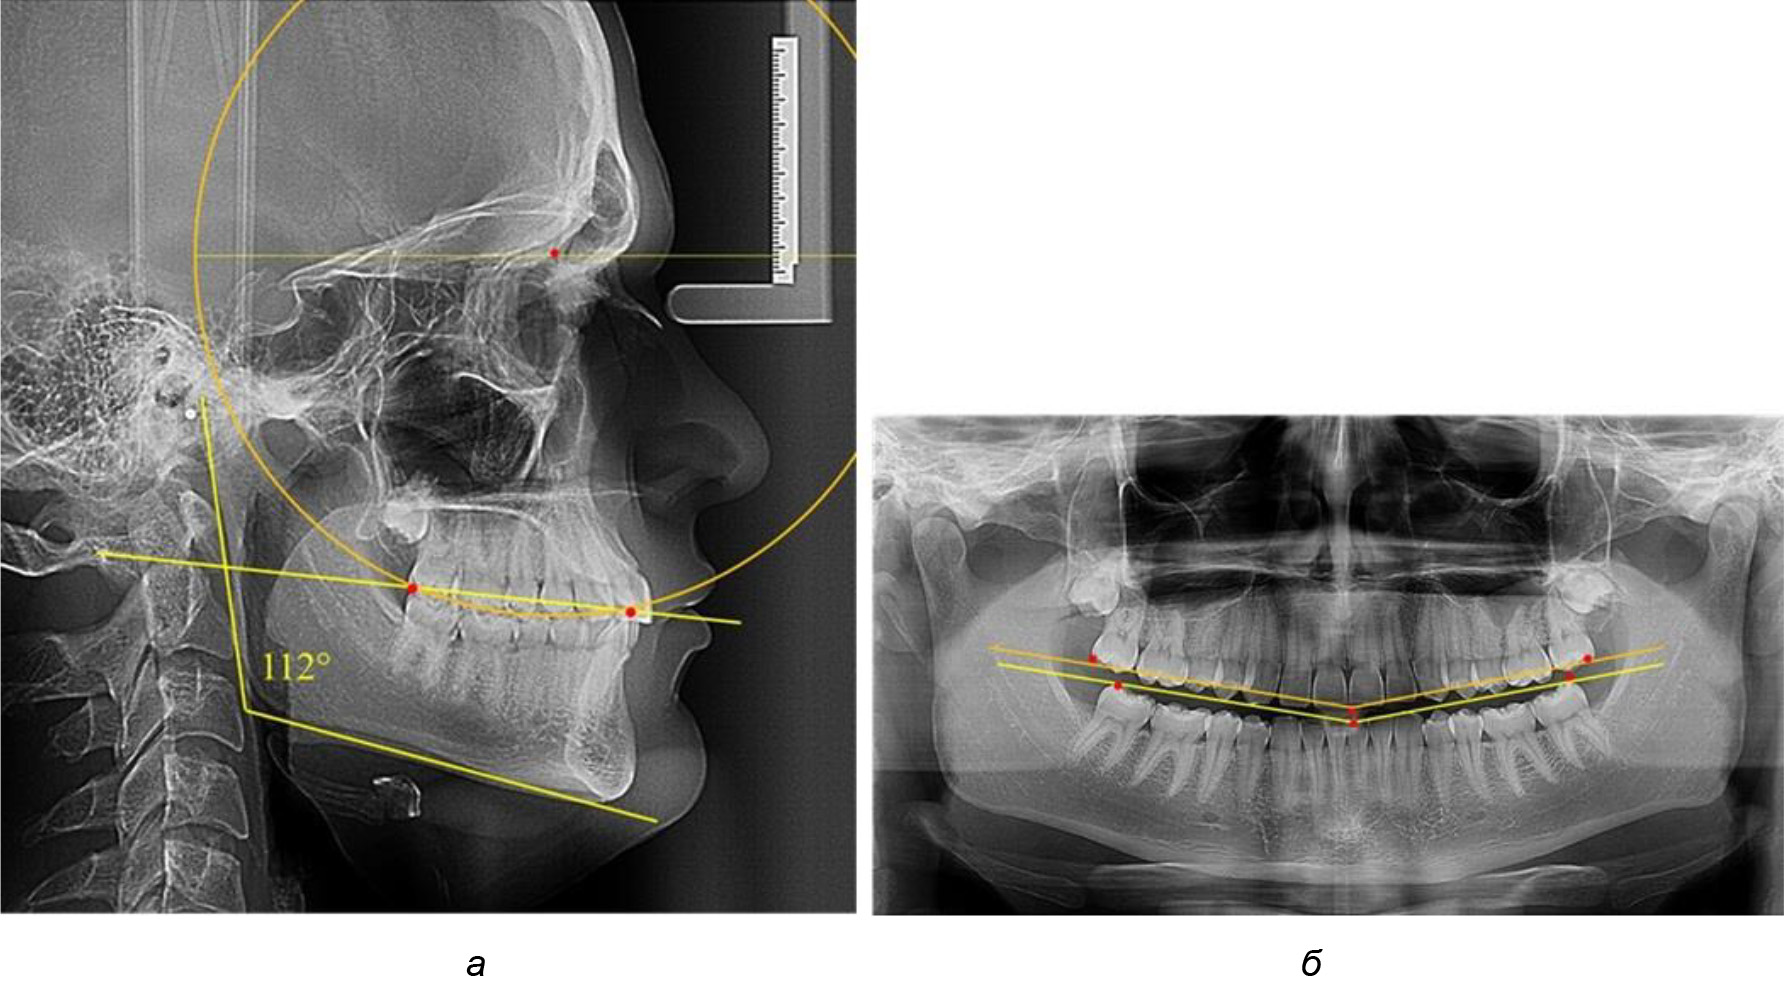

Деление величины радиуса круга к длине окклюзионной линии составило 1,623 ± 0,02. Таким образом, для определения радиуса окружности, соответствующей кривизне окклюзионного контура боковой ТРГ, необходимо измерить расстояние между передней и задней окклюзионными точками и последующим умножением полученной величины на число Фибоначчи (рис. 2).

Рис. 2. Особенности кривой Spee на ТРГ (а) и ОПТГ (б) у людей с признаками вертикального роста

На рентгенограммах людей 2-й подгруппы (30 человек с нейтральным типом роста) величина угла нижней челюсти в среднем составила (120,34 ± 2,19) ° и характеризовала нейтральный тип нижней челюсти.

Глубина кривой Spee в среднем по 2-й подгруппе составил (3,54 ± 0,58) мм, что было незначительно меньше, чем при анализе аналогичного показателя 1-й подгруппы.

Достоверных различий с показателями, полученными при анализе ТРГ и ОПТГ, нами не отмечено (р ˃ 0,05). Деление величины радиуса круга к длине окклюзионной линии составило 1,612 ± 0,02, что, так же как и в 1-й подгруппе, было близким по значению к числу Фибоначчи (1, 618).